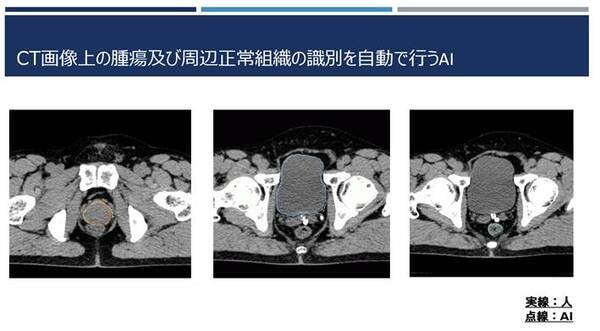

NVIDIAがリアルタイムの放射線治療を目指して医療分野で連携 AIが腫瘍と周辺の正常な臓器の輪郭を識別 3枚目の写真・画像

NVIDIAがリアルタイムの放射線治療を目指して医療分野で連携 AIが腫瘍と周辺の正常な臓器の輪郭を識別